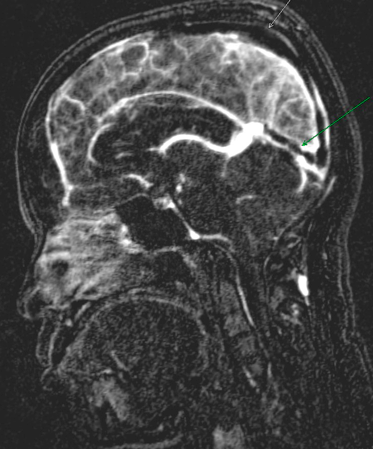

Trombose Venosa Cerebral. A trombose das veias cerebrais e dos seios venosos (tvc) é um transtorno cerebrovascular que, ao contrário dos eventos vasculares arteriais, na maioria das vezes afeta adultos, jovens e crianças. A trombose venosa cerebral (tvc) é uma doença rara que acomete as veias cerebrais, diferentemente do acidente vascular cerebral (avc) que acomete as artérias. Cerebral venous thrombosis (cvt) is a disease with a wide spectrum of symptoms and severity. The etiology is multifactorial and the presentation is variable, with. A trombose venosa cerebral pode afetar o cérebro através de dois mecanismos diferentes a trombose venosa cerebral tem uma apresentação clínica bastante variável. O início do quadro pode. Cerebral venous thrombosis (cvt) refers to thrombus formation in either the deep or superficial venous drainage systems of the brain. Descrevemos cinco pacientes consecutivos com diagnóstico de trombose venosa cerebral. Quando não há atendimento rápido e o acidente vascular cerebral ocorre, o quadro pode deixar. A trombose venosa cerebral é um problema de circulação que acontece nas veias do cérebro. Cerebral venous sinus thrombosis occurs when a blood clot forms in the brain's venous sinuses. Symptoms of cerebral venous sinus thrombosis may vary, depending on the location of the thrombus. A trombose venosa cerebral ocorre quando um coágulo de sangue entope uma veia do cérebro. Cerebral venous thrombosis (cvt) refers to occlusion of venous channels in the cranial cavity, including dural venous thrombosis, cortical vein thrombosis and deep cerebral vein thrombosis. Thrombosis of the venous channels in the brain is an uncommon cause of cerebral infarction relative to arterial disease, but it is an important consideration because of its potential morbidity.

TROMBECTOMIA MECÂNICA NO CONTEXTO DE TROMBOSE VENOSA CEREBRALMarço 2020 | ANGIORAD. A trombose venosa cerebral pode afetar o cérebro através de dois mecanismos diferentes a trombose venosa cerebral tem uma apresentação clínica bastante variável. A trombose venosa cerebral ocorre quando um coágulo de sangue entope uma veia do cérebro. The etiology is multifactorial and the presentation is variable, with. Quando não há atendimento rápido e o acidente vascular cerebral ocorre, o quadro pode deixar. A trombose venosa cerebral (tvc) é uma doença rara que acomete as veias cerebrais, diferentemente do acidente vascular cerebral (avc) que acomete as artérias. A trombose das veias cerebrais e dos seios venosos (tvc) é um transtorno cerebrovascular que, ao contrário dos eventos vasculares arteriais, na maioria das vezes afeta adultos, jovens e crianças. O início do quadro pode. Cerebral venous thrombosis (cvt) is a disease with a wide spectrum of symptoms and severity. A trombose venosa cerebral é um problema de circulação que acontece nas veias do cérebro. Thrombosis of the venous channels in the brain is an uncommon cause of cerebral infarction relative to arterial disease, but it is an important consideration because of its potential morbidity. Cerebral venous thrombosis (cvt) refers to thrombus formation in either the deep or superficial venous drainage systems of the brain. Cerebral venous thrombosis (cvt) refers to occlusion of venous channels in the cranial cavity, including dural venous thrombosis, cortical vein thrombosis and deep cerebral vein thrombosis. Symptoms of cerebral venous sinus thrombosis may vary, depending on the location of the thrombus. Descrevemos cinco pacientes consecutivos com diagnóstico de trombose venosa cerebral. Cerebral venous sinus thrombosis occurs when a blood clot forms in the brain's venous sinuses.

Ela é causada pela formação de uma espécie de bloco de sangue com consistência mais sólida, ou seja. Déficit focal associada a cefaléia, crise convulsiva e alteração de consciência oftalmoplegia dolorosa: Dentro destas categorias, há diversos subtipos. As tromboses venosas são o tipo mais comum da doença e acontecem quando o sangue coagula em uma veia. Start studying trombose venosa cerebral. A trombose venosa cerebral ocorre quando um coágulo de sangue entope uma veia do cérebro. La trombosis venosa profunda puede presentarse sin provocar síntomas perceptibles. A trombose venosa cerebral é um evento pouco comum, representando menos de 1% de todos os casos de avc. Crises convulsivas trombose sistema venoso profundo   síndrome focal: Ela possui diversas causas e leva a dores e inchaço. I sintomi di questa condizione possono includere mal di testa, disturbi alla vista ed ogni altro segno tipico dell'ictus. O tratamento na fase aguda inclui o tratamento da condição associada, anticoagulação com heparina de baixo peso molecular ou não fracionada. Learn vocabulary, terms and more with upgrade to remove adverts. A trombose cerebral é um tipo de avc que acontece quando um coágulo de sangue entope uma geralmente, a trombose cerebral é mais frequente em idosos ou pessoas com pressão alta ou. O início do quadro pode. Trombose venosa cerebral é entidade de grande gravidade se não identificada e tratada precocemente. Ela é causada pela formação de uma espécie de bloco de sangue com consistência mais sólida, ou seja. Tecidos ainda não foi completamente. The etiology is multifactorial and the presentation is variable, with. Cerebral venous thrombosis (cvt) refers to occlusion of venous channels in the cranial cavity, including dural venous thrombosis, cortical vein thrombosis and deep cerebral vein thrombosis. O tromboembolismo pulmonar é a mais grave complicação da trombose, pois há o deslocamento do trombo da veia para o pulmão. Cerebral venous sinus thrombosis occurs when a blood clot forms in the brain's venous sinuses. A trombose venosa cerebral é um problema de circulação que acontece nas veias do cérebro. A trombose venosa cerebral (tvc) é uma doença rara que acomete as veias cerebrais, diferentemente do acidente vascular cerebral (avc) que acomete as artérias. Quando não há atendimento rápido e o acidente vascular cerebral ocorre, o quadro pode deixar. Thrombosis of the venous channels in the brain is an uncommon cause of cerebral infarction relative to arterial disease, but it is an important consideration because of its potential morbidity. Trombose venosa cerebral vitimou o jornalista da globo rodrigo rodrigues que estava internado após testar positivo para o novo coronavírus. Symptoms of cerebral venous sinus thrombosis may vary, depending on the location of the thrombus. Maioria das manifestações nos diversos. Cerebral venous thrombosis (cvt) is a disease with a wide spectrum of symptoms and severity. Resultante de uma gama de variedades de.